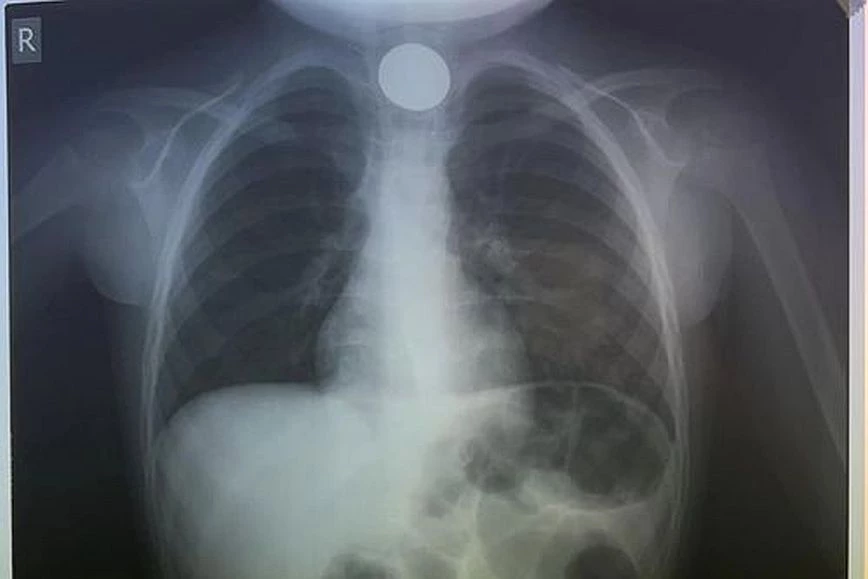

Περιπετειώδες ήταν το τελευταίο βράδυ του 2023 για μία οικογένεια στην Κρήτη, καθώς το 4χρονο παιδί τους, λίγες ώρες πριν την έλευση του 2024, κατάπιε κατά λάθος ένα κέρμα και μεταφέρθηκε εσπευσμένα στο νοσοκομείο του Ηρακλείου.

Ο μικρός κάτω από αδιευκρίνιστες συνθήκες κατάπιε κατά λάθος ένα κέρμα και όταν οι γονείς του αντιλήφθηκαν τι είχε συμβεί έσπευσαν να το μεταφέρθουν στο νοσοκομείο. Το παιδί δυσκολευόταν μεν να αναπνεύσει, αλλά ευτυχώς είχε τις αισθήσεις του.

Όταν έφτασαν στο ΠΑΓΝΗ, η πρώτη κίνηση των γιατρών ήταν να του κάνουν ακτινογραφία, για να δουν σε ποιο σημείο ακριβώς είχε σταθεί το νόμισμα και αμέσως μετά προχώρησαν στη διαδικασία αφαίρεσής του. Δεν πέρασε πολύς χρόνος και οι γιατροί κατάφεραν να αντιμετωπίσουν επιτυχώς το επείγον περιστατικό, λύνοντας ταχύτατα το πρόβλημα.

Μάλιστα σε σχετική ανάρτηση της Ωτορινολαρυγγολογικής Κλινικής του νοσοκομείου αναφέρεται το περιστατικό μαζί με ευχές για μια καλή χρονιά: «Αποχαιρετάμε το 2023 με επείγουσα αφαίρεση σε κατάποση κέρματος σε 4χρονο. Καλή Χρονιά».